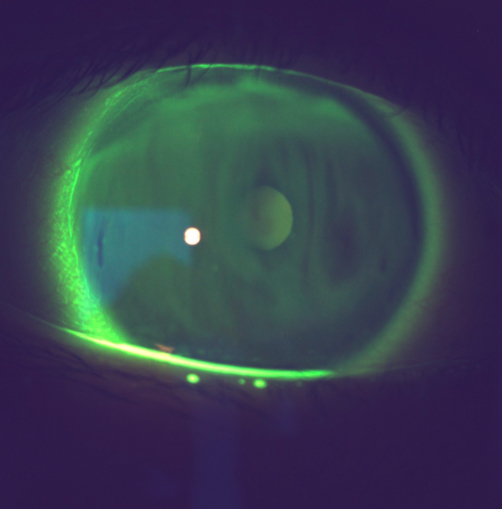

What do you use fluroscein for?

Corneal staining caused by dryness or abrasion

How do use corneal staining?

instil fluroscein

Use cobalt blue and written filter

Look with wide beam and low mag

Then scan using a parallel piped and x16 mag

Check whole cornea

Record by drawing

What’s going on here?

Corneal staining

Tear break-up

Dryness

Punctate staining